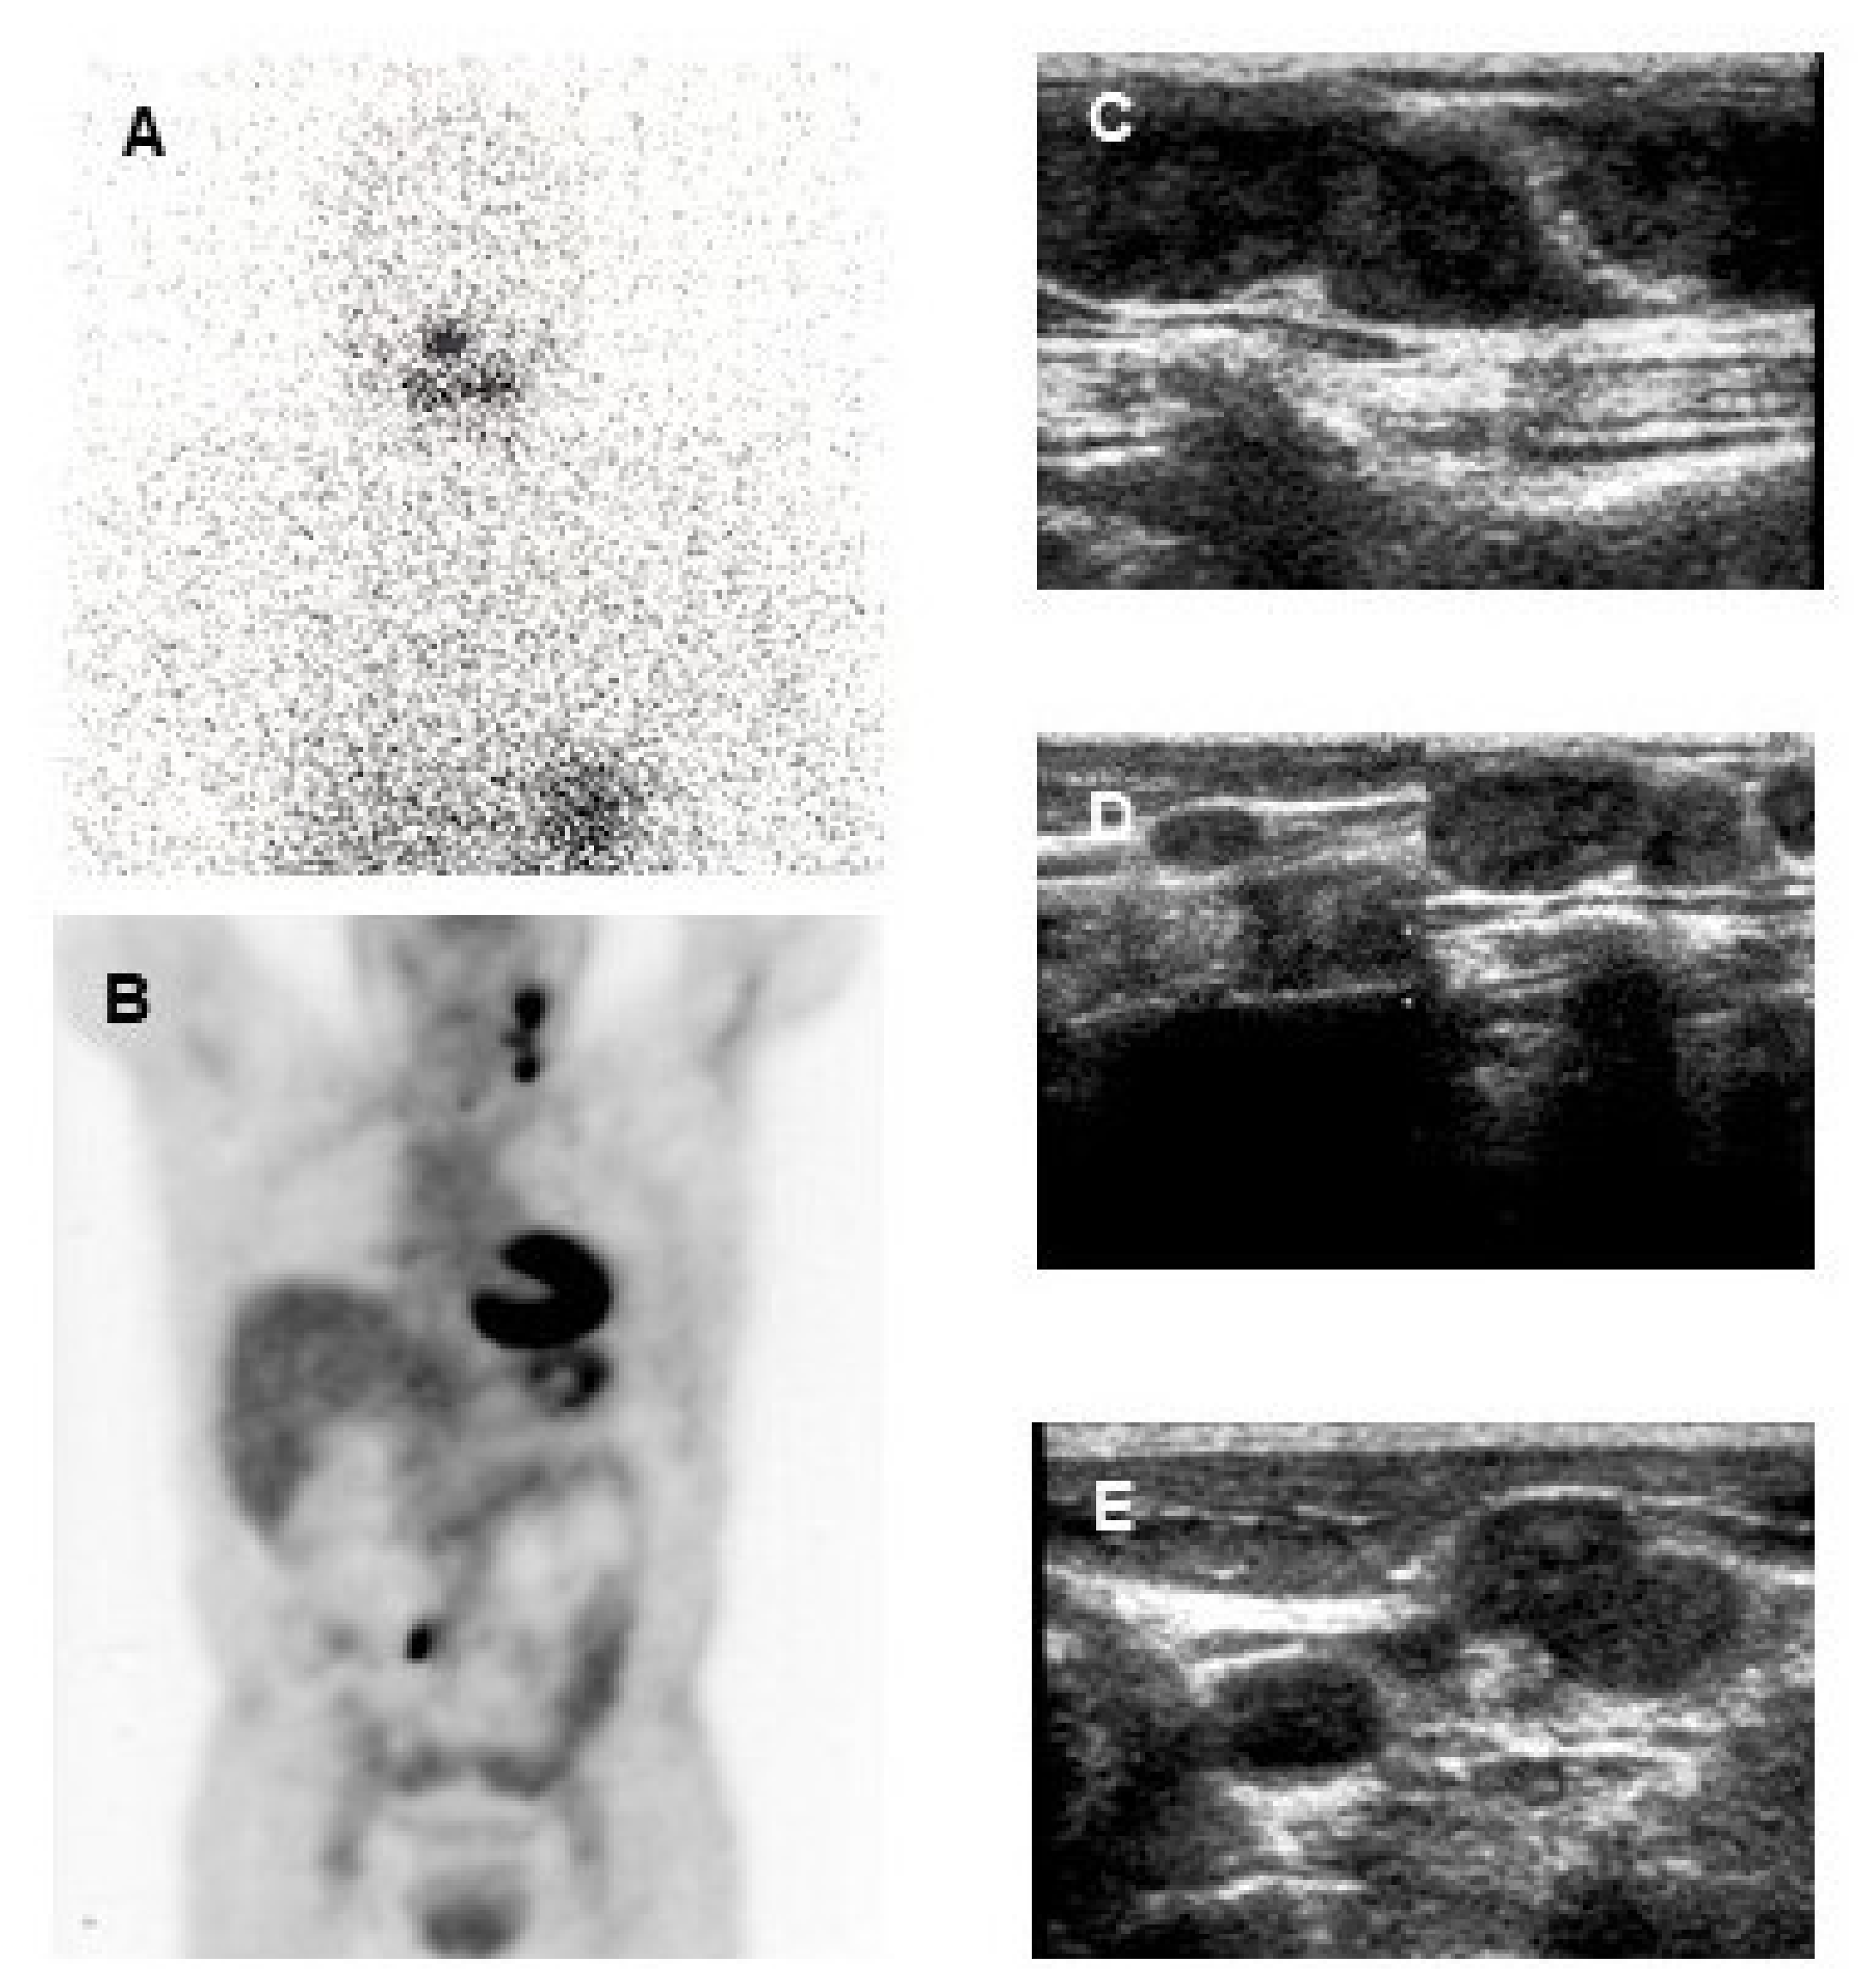

8.3. 18F-FDG PET/CT in Patients with Structural Disease

- Leboulleux, S.; El Bez, I.; Borget, I.; Elleuch, M.; Déandreis, D.; Al Ghuzlan, A.; Chougnet, C.; Bidault, F.; Mirghani, H.; Lumbroso, J.; et al. Postradioiodine treatment whole-body scan in the era of 18-fluorodeoxyglucose positron emission tomography for differentiated thyroid carcinoma with elevated serum thyroglobulin levels. Thyroid 2012, 22, 832–838. [Google Scholar] [CrossRef] [PubMed]